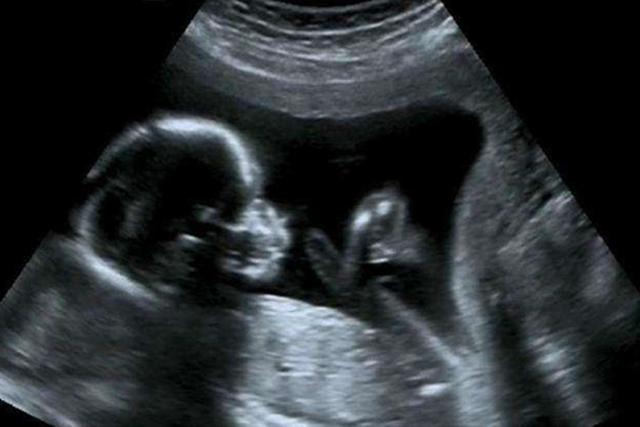

B超检查可以说是判断胎儿性别最准确、最科学的方式之一了,它可以透过孕妇的肚子观察腹中胎儿的生殖器官。

但是,大家也别把B超检查“神化”,它的影响因素较多,也是有一定概率导致判断错误的。

缜密点说,B超只能是准确性相对较高,但不能完全作为结论。

要想准确判断性别,做B超检查时就需要能清晰看到胎儿的生殖器官。

但胎儿在孕肚中是活动的,经常会翻身、转圈,伸胳膊伸腿更是常事,很容易把生殖器官遮盖住。

因此,如果胎儿不配合,那B超检查同样很难看清生殖器官。若医生经验不丰富,就可能由于看不到生殖器官而认定是女孩。

大家应该都见过B超影像,画面灰蒙蒙的,呈现黑白色。

作为非专业人士的我们,可能最多就只能看出胎儿的四肢和头部了,其他部分根本分辨不出。

经验不足的医生看到的和我们差不多,若生殖器官部位不那么清晰,就很有可能把脐带误认为是生殖器官,导致判断错误。